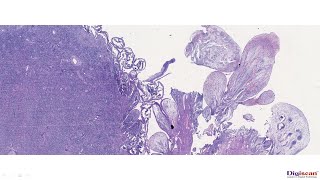

LEIOMYOSARCOMA (Female Genital Tract)

LEIOMYOSARCOMA (Female Genital Tract) This video mainly focuses on Leiomyosarcoma. Hope it is useful. DR IHTESHAM UD DIN QURESHI PROFESSOR ...

Dr. Ihtesham Qureshi